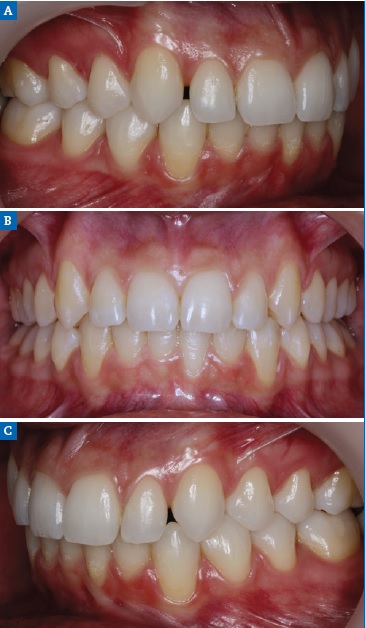

Figure 11 Case 2: Intraoral views of the (A) right, (B) frontal, and (C) left aspects after the orthodontic treatment.

A 15-year-old patient presented with unilateral MLIA and microdontia (Figure 9). The left maxillary canine erupted mesially from its normal position, while the right maxillary lateral incisor was conical. Both central incisors were tipped to the left and associated with occlusal plane canting to the left. There was also an evident Bolton’s anterior discrepancy of 74.1 % (13, 12, 11, 21, 23, 24 / 43,42, 81, 71, 32, 33) due to maxillary asymmetric agenesis, a canine in place of the lateral incisor, and a conical contralateral (Figure 10). And due to agenesis of the mandibular central incisors and the presence of correspondent deciduous teeth. After the orthodontic treatment (Figure 11), the complexity of the asymmetric case required digital smile planning (Figure 12) and a diagnosis wax-up (Figure 13) to plan and visually demonstrate the desired result to the patient.